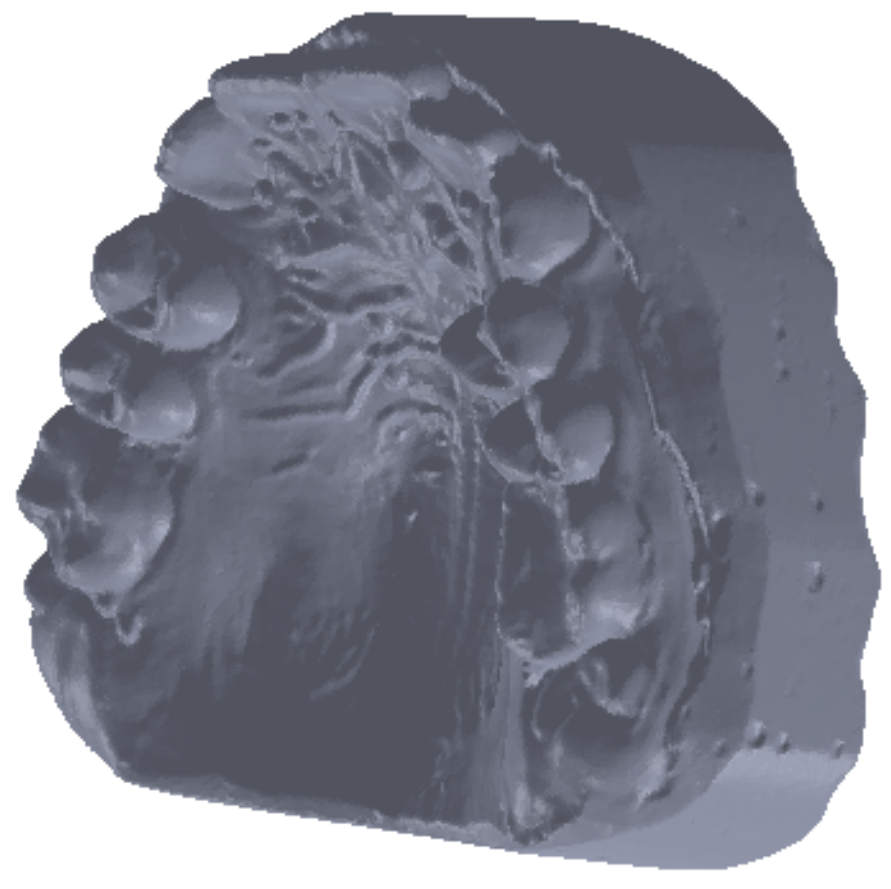

To obtain the final model, 30 successive scans were performed. Then, we obtained the final model of the scan operation. Figure 5 shows the common point cloud of the upper and lower images, which represents the raw, unprocessed model of the scanned maxillary.

Finally, we obtained a closed final surface, as shown in Figure 6.

Figure 5. Scanned image of the maxillary arch.